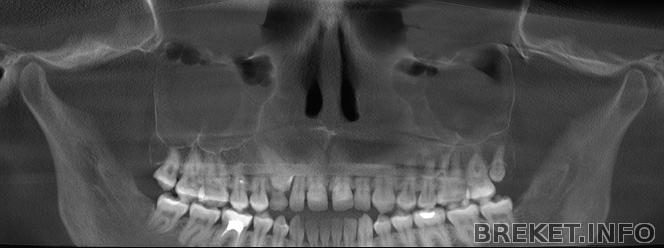

Решила тут сравнить КТ сразу после оп. по рассечению нёбного шва, сразу после расширения и после снятия аппарата.

тут уже есть небольшая диастема, которую раскручивают во время операции